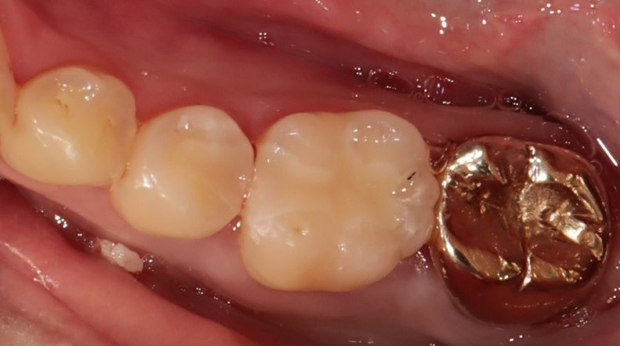

라미네이트